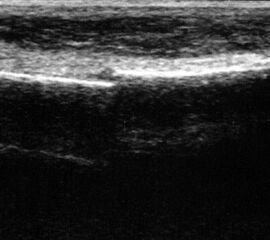

Achillessehne

Achillessehnenrupturen

Lagerung: Bauchlage, ggf. Sprunggelenk mittels Rolle unterlagert.

Schnittführung: LS über der Achillessehne, ggf. in leichter manueller Vorspannung der Achillessehne, damit diese parallel zum Schallkopf optimal eingestelt werden kann (Abb. 52).

Referenzstruktur: Direkt unter der Haut und der dünnen Subkutis liegt echogen und straff parallel die Achillessehne mit ihrem echogenen Peritendineum (Abb. 53), Tuber calcanei.